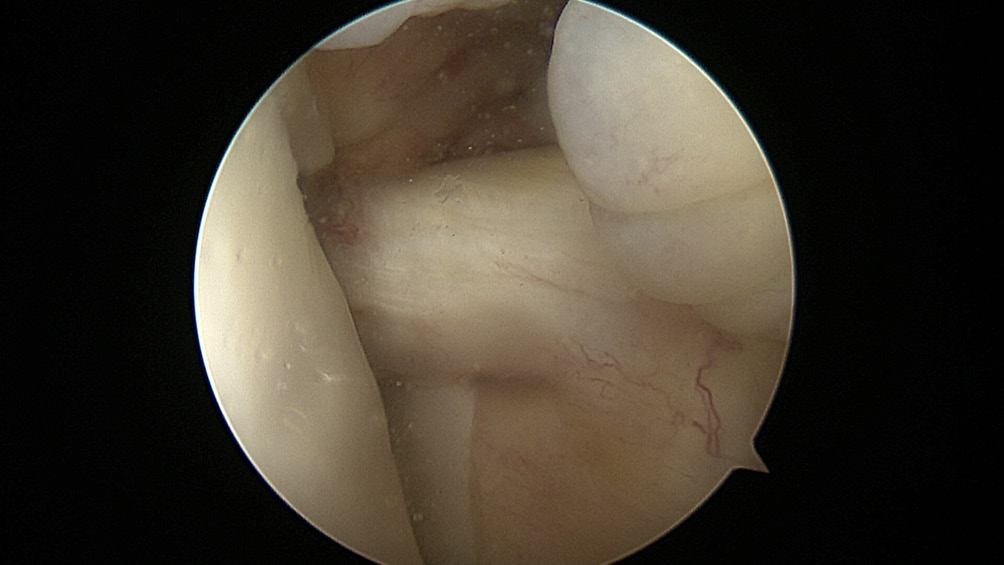

All the patients were operated on by the same team, using the same surgical technique and Neoligaments (Neoligaments) (Figure 1) or FiberTape (Biomet) (Figure 2) graft. It was fixed using Endobutton (Smith-Nephew, Watford, UK) on the femur and the interference screw, ComposiTCP30 (Biomet), on the tibia. It was prepared using the “outside-in” technique with the aimer device (Figure 3, Figure 4, Figure 5, Figure 6, Figure 7, Figure 8).